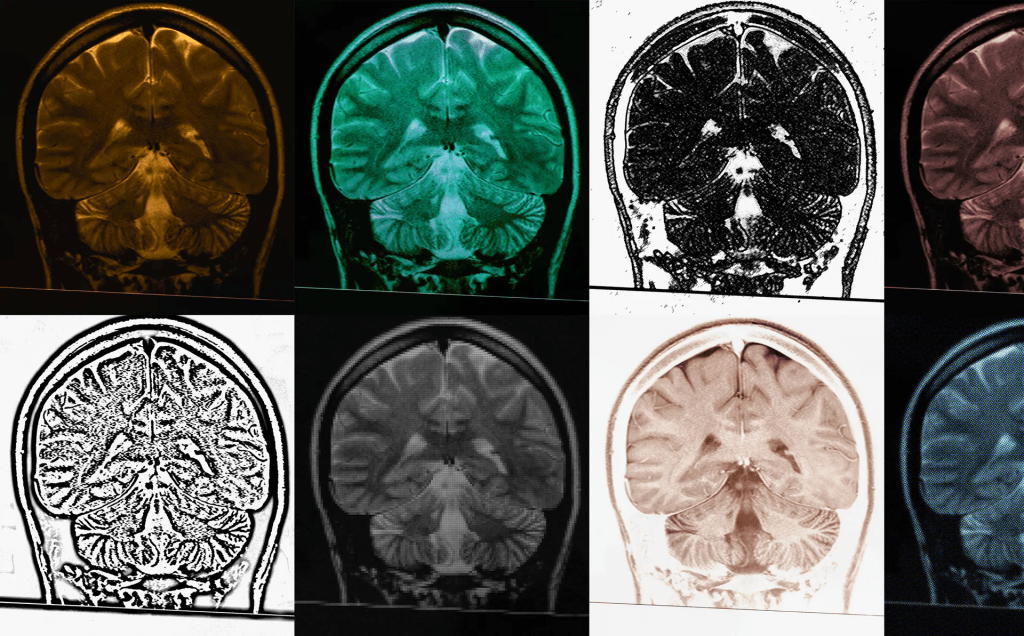

Knudsen believes that SSRIs owe their efficacy at least in part to boosting neuroplasticity. Writing in Molecular Psychiatry earlier this month, her team showed how they had tested this theory on people, thanks to a special kind of PET scan developed in the past few years. They recruited 32 people to take the SSRI escitalopram (also known by the brand name Lexapro) or a placebo for one month. Then they asked the people to take a PET scan at the end of the trial, and used radioactive tracers to track where in the brain new synapses were forming.

But until about seven years ago, scientists couldn’t replicate these studies in humans, since there was no way to measure synaptic density without cutting out brain tissue. Then in 2016, researchers developed a way to detect synaptic activity in live human brains during PET scans. These scans detect light emitted by radioactive “labels” designed to stick to specific proteins. The patient receives an injection of these radioactive markers, which diffuse to the target proteins in the brain. The scan reveals a map of where exactly those proteins are.

Scientists quickly began using the PET method to study disorders like Alzheimer’s and schizophrenia, convincing Knudsen of its power for mental health studies. So her team organized a double-blind, randomized clinical trial in which healthy participants would receive a standard 20-milligram SSRI or a placebo daily. After three to five weeks, the team would collect PET scans of the synapses in each person’s neocortex and hippocampus. In this case, the labels were designed to stick to a protein at the connection between neurons. Tracing them would map out the brain’s synapses, allowing scientists to measure synaptic density.

PET scans are becoming an unparalleled resource for measuring wiring in human brains. “It’s very rare to have the ability to do an experiment like this,” Nord says. “They’re giving us a quite unusual window into the processes that are happening in this treatment.” Knudsen’s team has also used them to investigate psilocybin’s effects, and another team has studied ketamine’s. “What this paper is really showing is that you can detect these new connections being formed,” Roiser adds.